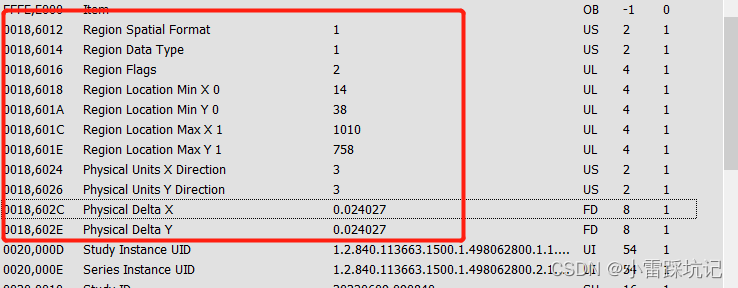

PhysicalDeltaX ,PhysicalDeltaY 就是要我们要找寻的字段

特别注意一下这个 PhysicalDeltaX ,PhysicalDeltaY 值需要同时 *10,才是最终像素

我是用的java dcm4che 解析的,这个时候直接解析对应的Tga值,是解析不出来的.

先解析对应的sequence值,然后在sequenc值里面再解析对应的tag值